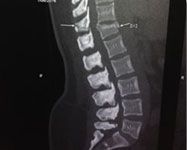

Minimally Invasive Spinal Trauma Fixation